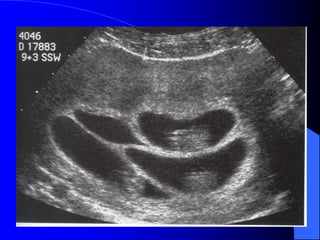

III. Phoâi hoïc: söïphaân chia khoâng hoøan toøan cuûa dóa phoâi giai ñoïan treã ôû song thai moät hôïp töû (ít nhaát laø 13 ngaøy sau thuï thai) IV. Daáu hieäu sieâu aâm: - Hai ñaàu laø moät daïng ñaëc bieät cuûa song thai dính: moät thaân vaø hai ñaàu. - Ña oái cuõng thöôøng gaëp.

V. Kieåm soaùtlaâm saøng: - Kieåm tra baèng sieâu aâm bao goàm caû sieâu aâm tim. Sieâu aâm kieåm tra ñònh kyø phaùt hieän phuø thai vaø ñaùnh giaù ñoä taêng tröûông. - Tieân löôïng ñöôïc hoäi chaån giöõa baùc só saûn khoa vaø baùc só phaãu nhi. - Thai cheát trong töû cung chieám khoûang 30%.